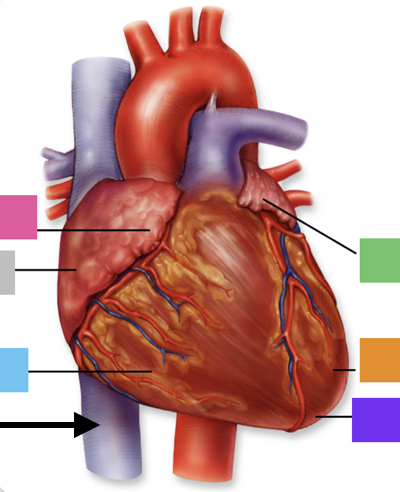

coronary (atrioventricular) sulcus

interatrial septum

interventricular septum

anterior interventricular sulcus

posterior interventricular sulcus

superior vena cava

inferior vena cava

pulmonary trunk

left pulmonary artery

left pulmonary veins

(branches of) right pulmonary artery

right pulmonary veins

ascending aorta

right coronary artery

posterior interventricular artery

left coronary artery

anterior interventricular artery

circumflex artery